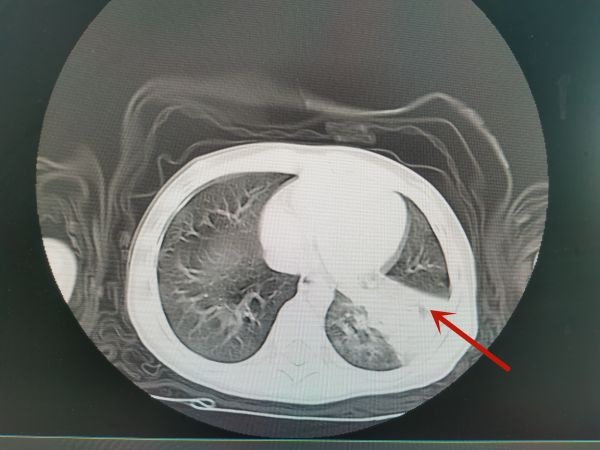

欣欣的CT检查显示肺部感染。

接诊医生陈静检查发现,小患者呼吸急促、浅快,口唇虽无明显发绀及吸凹征,但左肺听诊呼吸音减低,建议做一个肺部CT。结果显示,孩子左下肺有大片状密度增高影,部分实变,血气分析提示已经有低氧血症和呼吸性酸中毒,指脉氧饱和度降到90%,诊断为重症肺炎。好在家长送医及时,经过吸氧吸痰、抗炎抗感染及止咳化痰、退热补液等综合对症救治,患儿病情转危为安,症状逐渐缓解。

无独有偶,病房另一名10岁男孩轩轩,发热仅持续了1天就退了,但仍有咳嗽。可是退烧2天后,轩轩就再次出现高热,体温最高达39.2℃,同时咳嗽加重。在儿科门诊,轩轩检查胸部CT,发现左肺多发斑片状及团块状磨玻璃高密度影。